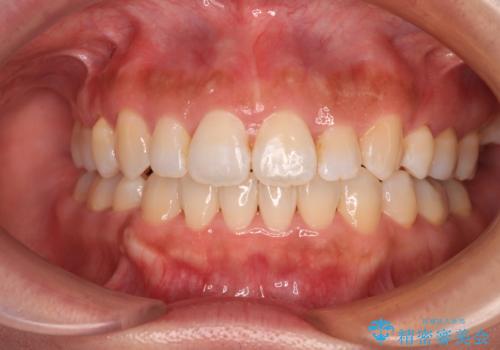

- 飛び出した前歯と全体的なデコボコを気にして来院された患者様です。

ワイヤーでもマウスピースでも治療可能でしたが、自己管理の重要なマウスピース矯正は自分には向かないとのことで、ワイヤー矯正で治療することとしました。

上下歯列全体を後方に移動させるため、親知らずは全て抜歯することにしました。